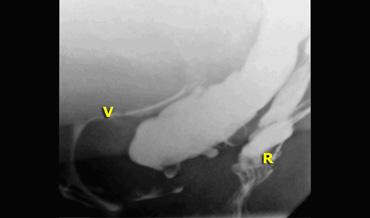

Hình ảnh bình thường khi nghỉ (bên trái); trong khi đại tiện có túi sa trực tràng bị đẩy xuống dưới bởi thoát vị ruột non.

Đôi khi thoát vị ruột non chỉ được xác định vào cuối quá trình đại tiện, sau nhiều lần rặn.

Thoát vị ruột non có thể bị đẩy về phía cửa âm đạo.

Nếu có túi sa trực tràng kèm theo, túi sa này có thể bị đẩy xuống dưới bởi thoát vị ruột non và cuối cùng được tống ra ngoài (hình).